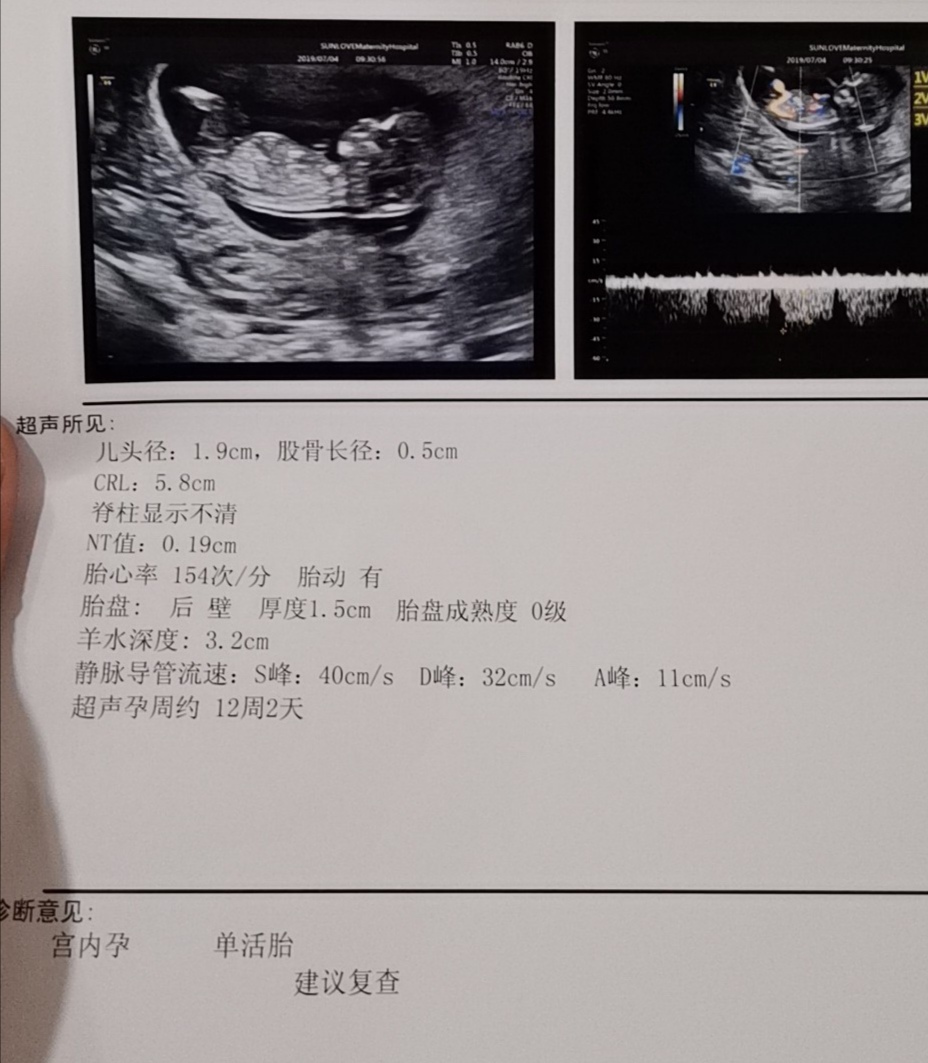

你做的这是什么检查,非常详细,我做的NT简直就是糊弄

沈磊[帖主]:12周的nt